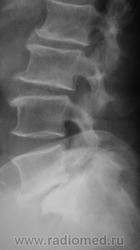

Спондилолистез L5-S1 - истинный, поэтому природа сама набедокуривши, сама и оберегает. Трудно представить безсимптомное течение, если бы это было последствием травмы. Очень рад, что Андрей Юрьевич приводит выдержки из Рейнберга. Судя по желтизне страниц - это первое издание.

По данному случаю:на мой взгляд, он является примером того, что попытки обяснить клинику(страдания пациента) только изменениями на R-граммах несостоятельны (если бы, у пациентки были жалобы,скажем на боли в области поясницы, сделали бы вывод-"что вы хотите?!-деформирующий спондилёз, да ещё спондилолистез- из-за этого и болит"). Думаю, многие сталкивались такими направлениями: "Направляеться на R-графию пояснично-крестцового отдела позвоночника.D.S.:Исключить остеохондроз ".